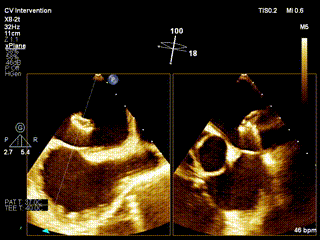

食道超声确认:分流器左房伞位于左房

超声可见左向右分流束